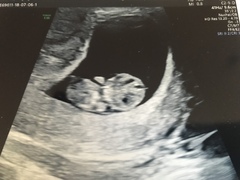

Just back from my scan ladies. Bub measured exactly what we thought 9+3, good heartbeat, two arms and two little legs wriggling about! It was amazing to see bub move 😍 I’m so in love ❤️

@hayleyfx this is just beautiful! Massive congratulations! X

@hayleyfx congrats lovely x

What a beautiful scan picture @hayleyfx. How exciting 😬. Congratulations and I’m glad it went well.